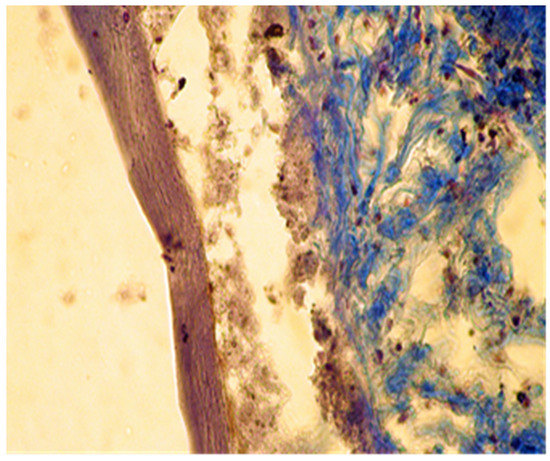

Figure 5. Group A. Buffer zone, consisting of fibroblast proliferation and collagen fiber synthesis. Col. Trichrome Masson, ×200.

In group A (implanted with MTA) we noticed a well-defined area of peripheral necrosis (surrounding the biomaterial) in which incompletely resorbed MTA fragments and an intense influx of leukocytes consisting of macrophages, histiocytic cells, and neutrophils were present, together with a high number of fibroblasts and collagen fibers (Figure 4 and Figure 5).